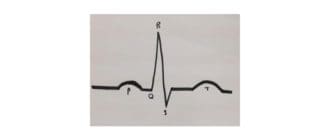

心房細動は、不規則な時間に心臓を鼓動させる心臓の状態である。心臓のビートは、鎖様の反応で心臓のある部分から別の部分にメッセージを送信する電気伝導システムの結果である。 人が心房細動(A-fib)を有する場合、電気信号は通 […]